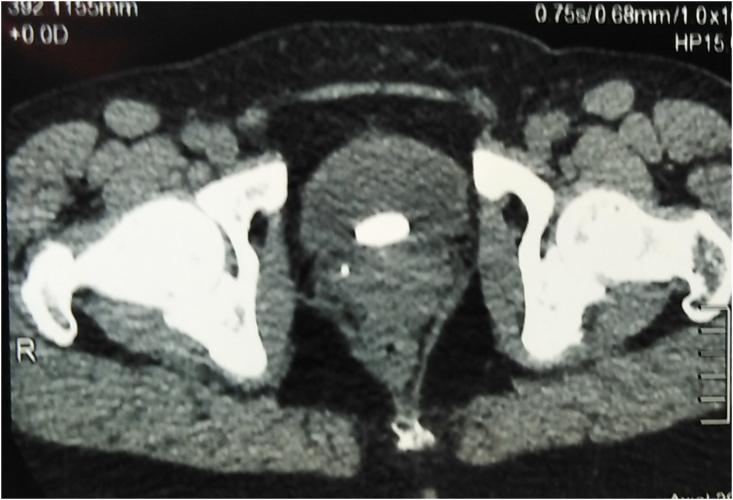

An intrauterine device (IUD) perforating the uterus and bladder and creating a nidus for stone formation is rarely described in the international literature. A 50-year-old woman was referred to our department for 6 months history of suprapubic pain and pollakiuria without fever. Ultrasound, X-ray examination and abdominopelvic scanner confirmed an IUD perforating the uterus and the bladder. The stone on the perforating ectopic IUD was successfully removed with YAG Holmium Laser and the IUD was extracted without complications with the aid of a transurethral resectoscope.

宫内节育器(IUD)穿孔进入子宫和膀胱并形成结石病灶的情况在国际文献中鲜有报道。一名50岁女性因耻骨上疼痛和尿频6个月病史被转诊至我院,无发热症状。超声、X线检查及腹部盆腔扫描仪证实一枚宫内节育器穿孔进入子宫和膀胱。通过钇铝石榴石激光成功取出穿孔异位宫内节育器上的结石,并借助经尿道电切镜顺利取出宫内节育器,未发生并发症。